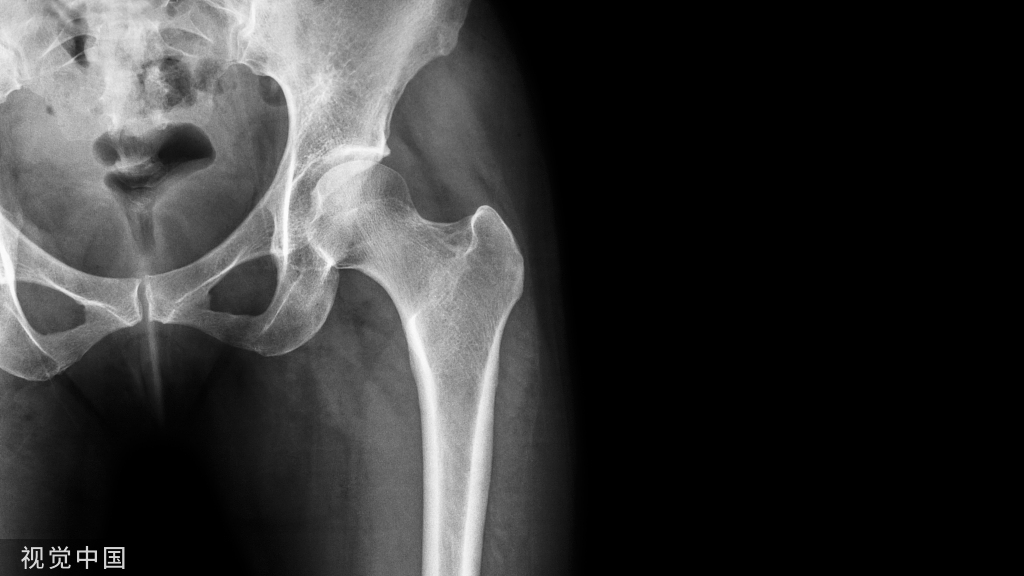

颈椎后路单开门丝线悬吊术示意图

颈椎后路椎板切除减压侧块螺钉内固定术示意图